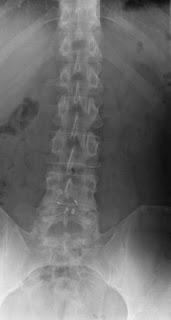

The X-Rays following my 3 month visit to the surgeon were finally sent to me and I've posted them underneath.

Here are the X-rays:-

(AP- X-Ray courtesy of BCH)